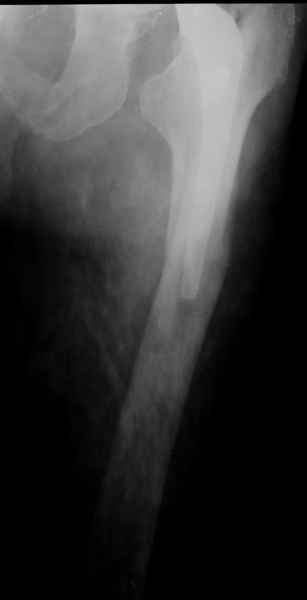

Хочется показать два подобных случая, П-ка Зубарева 72 лет и п-т Гладковский 80 лет. Сразу принимаю замечание, что это были ножки цементной фиксации, просто под руками не было бесцементника.